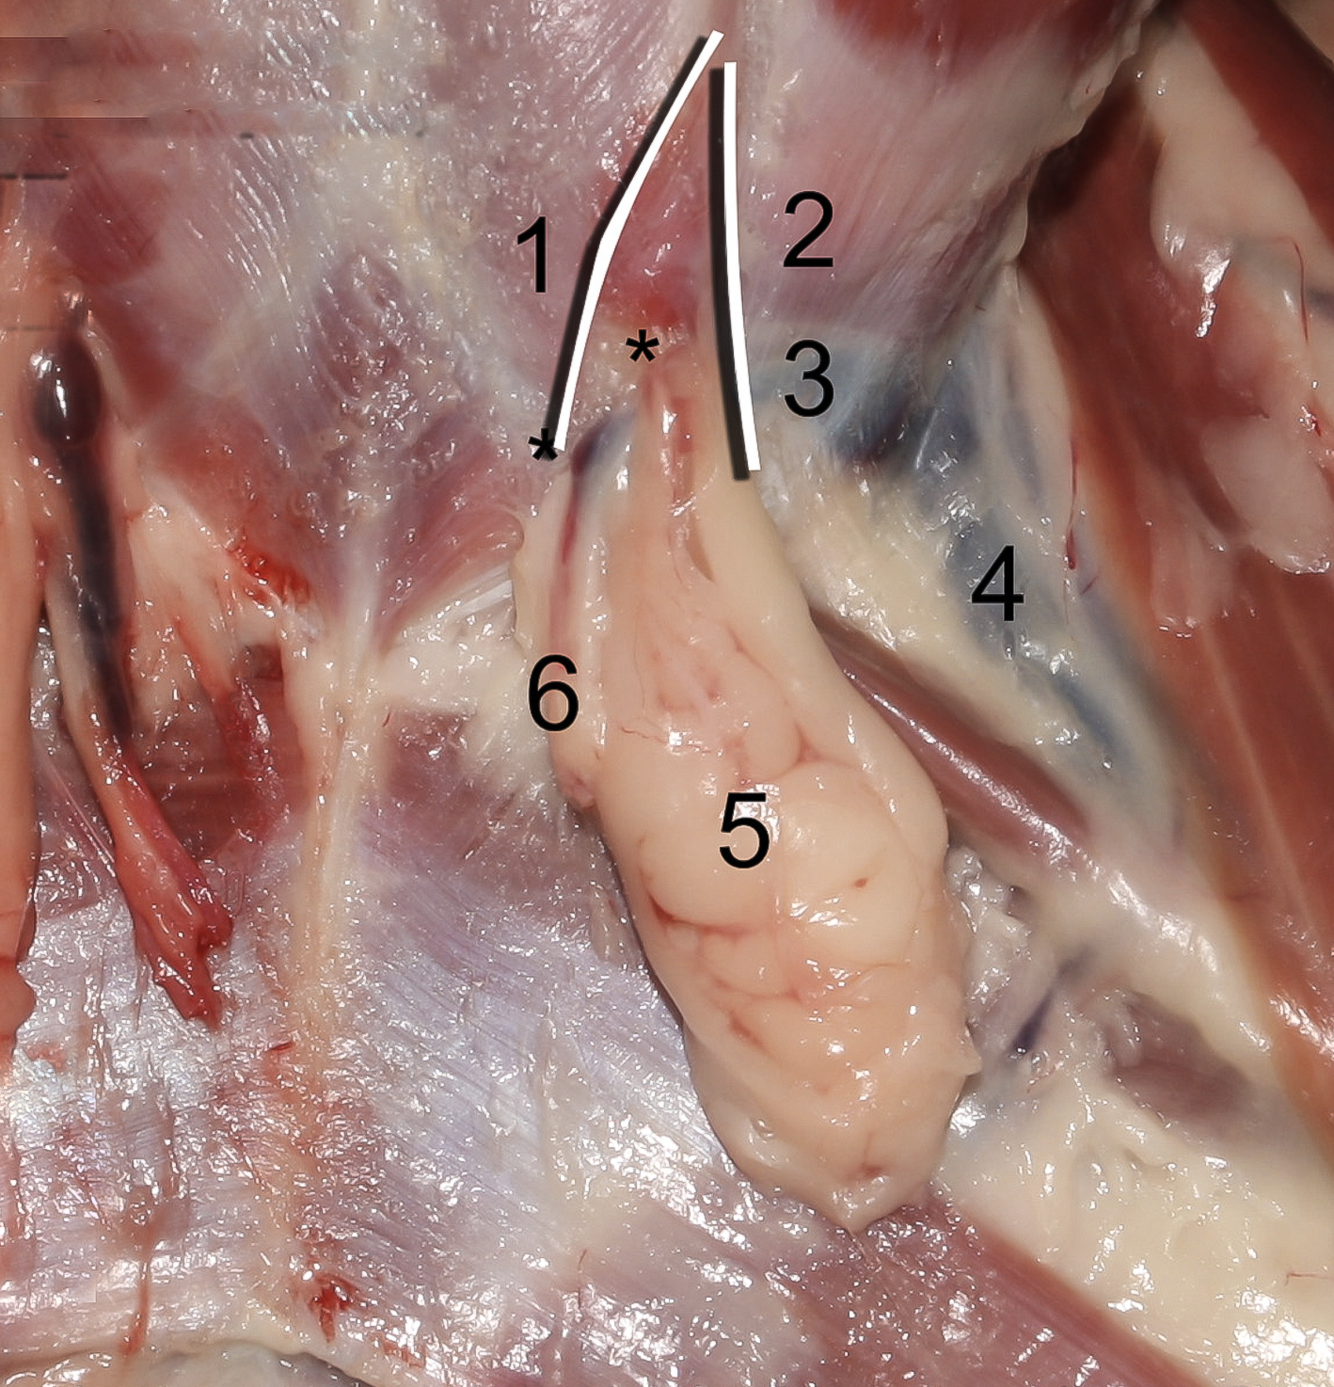

11

Q

1

A

Crus mediale

12

Q

2

A

Crus laterale

13

Q

3

A

A./v. pudenda externa

14

Q

5

A

Processus vaginalis

15

Q

6

A

M. obliquus internus abdominis